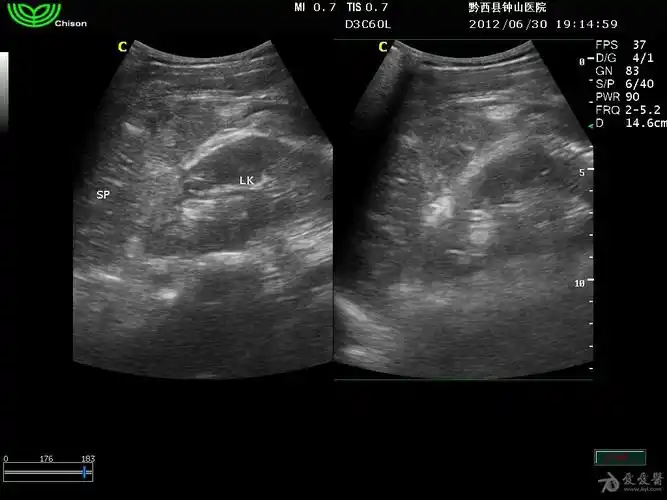

1小时前做的脾破裂出血 - 超声医学讨论版 - 爱爱医医学论坛